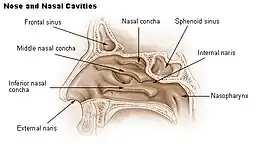

F. Bony anatomy of the nose

In the upper portion of the nose, the paired nasal bones attach to the frontal bone. Above and to the side (superolaterally), the paired nasal bones connect to the lacrimal bones, and below and to the side (inferolaterally), they attach to the ascending processes of the maxilla (upper jaw). Above and to the back (posterosuperiorly), the bony nasal septum is composed of the perpendicular plate of the ethmoid bone. The vomer bone lies below and to the back (posteroinferiorly), and partially forms the choanal opening into the nasopharynx, (the upper portion of the pharynx that is continuous with the nasal passages). The floor of the nose comprises the premaxilla bone and the palatine bone, the roof of the mouth.

The nasal septum is composed of the quadrangular cartilage, the vomer bone (the perpendicular plate of the ethmoid bone), aspects of the premaxilla, and the palatine bones. Each lateral nasal wall contains three pairs of turbinates (nasal conchae), which are small, thin, shell-form bones: (i) the superior concha, (ii) the middle concha, and (iii) the inferior concha, which are the bony framework of the turbinates. Lateral to the turbinates is the medial wall of the maxillary sinus. Inferior to the nasal conchae (turbinates) is the meatus space, with names that correspond to the turbinates, e.g. superior turbinate, superior meatus, et alii. The internal roof of the nose is composed by the horizontal, perforated cribriform plate (of the ethmoid bone) through which pass sensory filaments of the olfactory nerve (cranial nerve I); finally, below and behind (posteroinferior) the cribriform plate, sloping down at an angle, is the bony face of the sphenoid sinus.

Internal nasal anatomy

In the midline of the nose, the septum is a composite (osseo-cartilaginous) structure that divides the nose into two similar halves. The lateral nasal wall and the paranasal sinuses, the superior concha, the middle concha, and the inferior concha, form the corresponding passages, the superior meatus, the middle meatus, and the inferior meatus, on the lateral nasal wall. The superior meatus is the drainage area for the posterior ethmoid bone cells and the sphenoid sinus; the middle meatus provides drainage for the anterior ethmoid sinuses and for the maxillary and frontal sinuses; and the inferior meatus provides drainage for the nasolacrimal duct.

The internal nasal valve comprises the area bounded by the upper lateral-cartilage, the septum, the nasal floor, and the anterior head of the inferior turbinate. In the narrow (leptorrhine) nose, this is the narrowest portion of the nasal airway. Generally, this area requires an angle greater than 15 degrees for unobstructed breathing; for the correction of such narrowness, the width of the nasal valve can be increased with spreader grafts and flaring sutures.